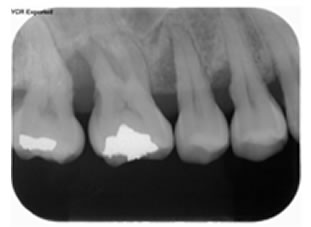

X-Ray(レントゲン)写真

骨の状況、またむし歯の状態、咬み合わせによる歯牙への負担をチェックします。